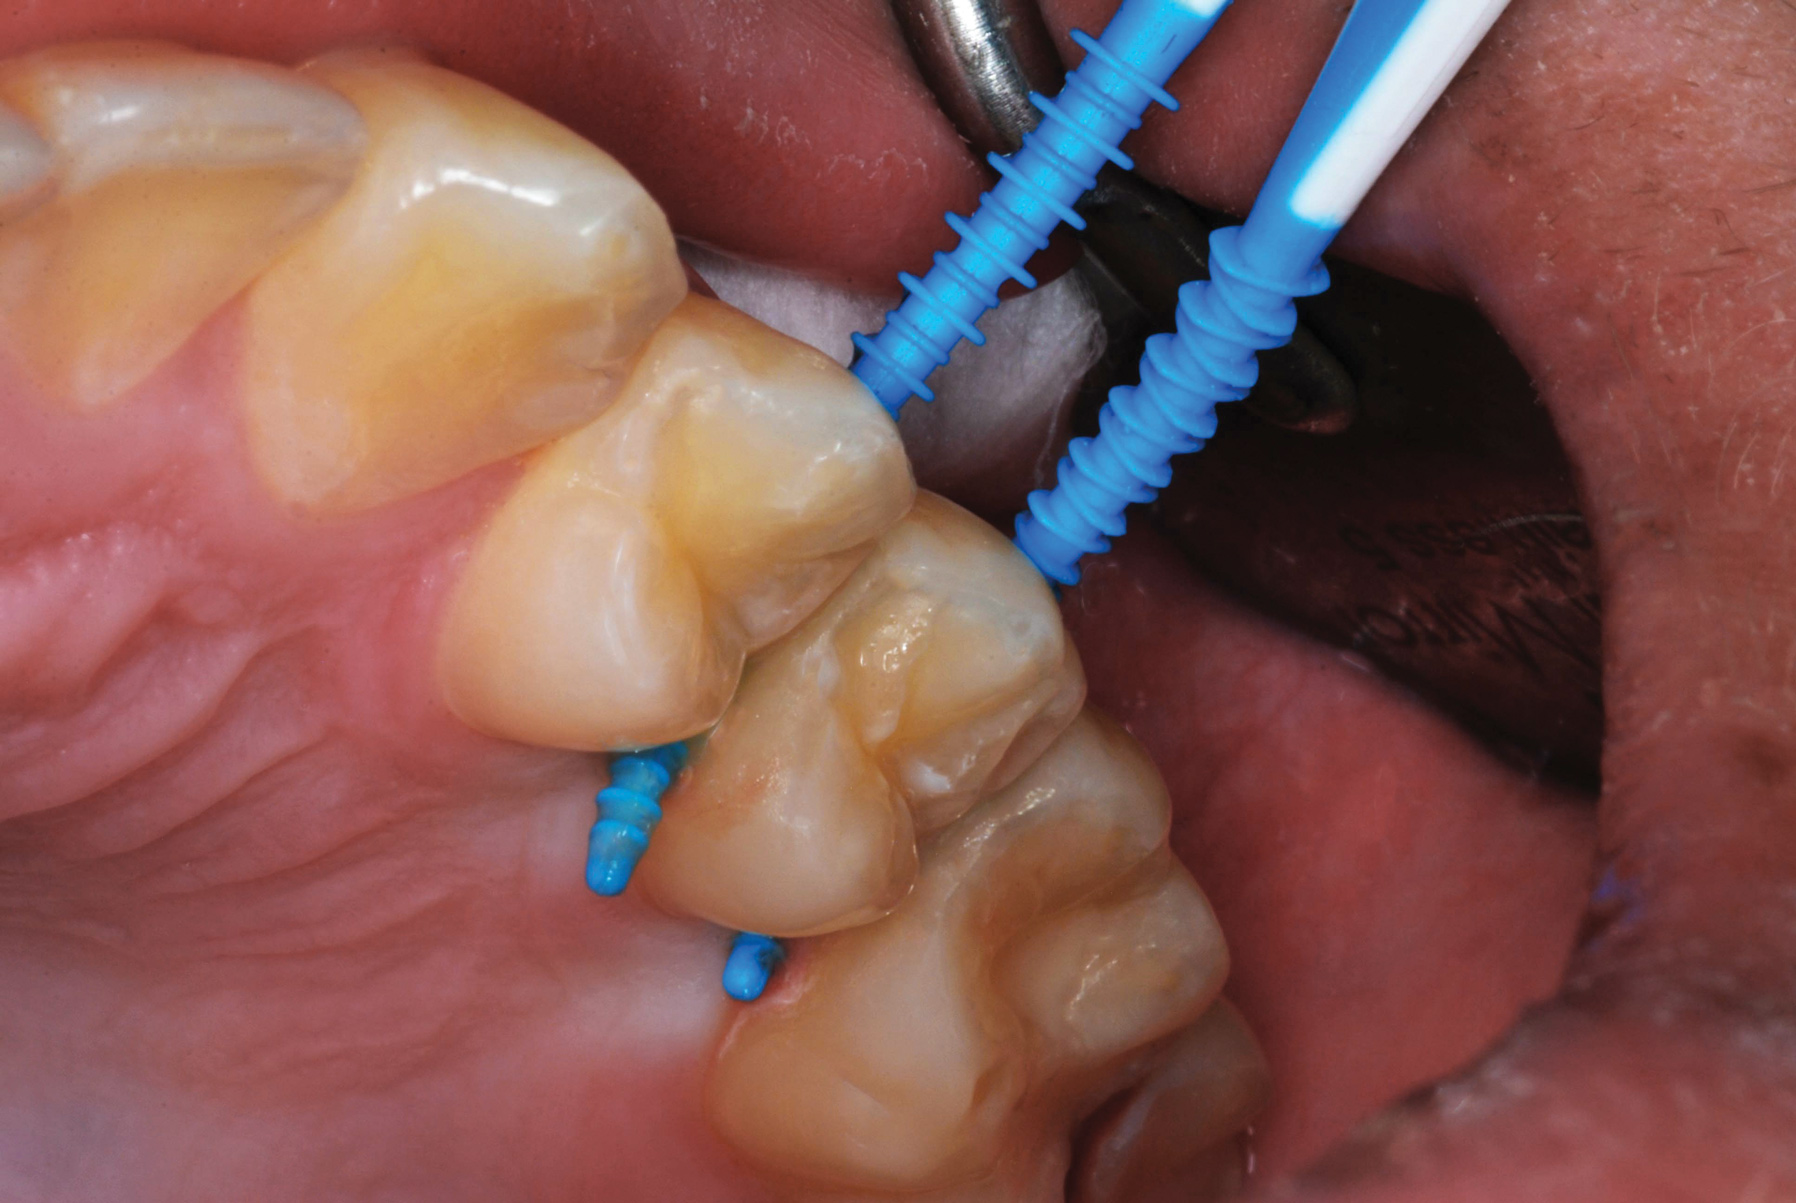

Figure 7 illustrates the use of thicker picks in premolar interproximal sites. Additionally, multiple picks can be used in one quadrant or in one proximal site with good isolation to maximize fluid saturation (Figure 9), which the authors have found to be an excellent time-saving strategy. Preventive or interceptive applications of SDF may also be effectively used in interproximal sites in orthodontic patients (Figure 10).

Fig 7. An example of the use of thicker picks for premolar interproximal sites.

Figure 7